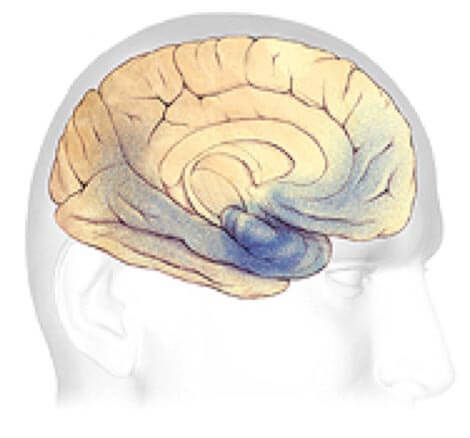

Alzheimer's disease leads to nerve cell death and tissue loss throughout the brain. Over time, the brain shrinks dramatically, affecting nearly all its functions.

These images show:

A brain with advanced Alzheimer's.

Progression Through the Brain

Plaques and tangles (shown in the blue-shaded areas) tend to spread through the cortex in a predictable pattern as Alzheimer's disease progresses. The rate of progression varies greatly. On average, a person with Alzheimer's lives four to eight years after diagnosis, but can live as long as 20 years, depending on other factors. The course of the disease depends in part on age at diagnosis and whether a person has other health conditions.

Mild to moderate Alzheimer's stages - generally last from 2 - 10 years.

Mild to Moderate Alzheimer's

In mild to moderate stages, brain regions important in memory and thinking and planning develop more plaques and tangles than were present in early stages. As a result, individuals develop problems with memory or thinking serious enough to interfere with work or social life. They may also get confused and have trouble handling money, expressing themselves and organizing their thoughts. Many people with Alzheimer's are first diagnosed in these stages.

As Alzheimer's progresses, individuals may experience changes in personality and behavior and have trouble recognizing friends and family members.

Plaques and tangles also spread to areas involved in:

Speaking and Understanding Speech

Your sense of where your body is in relation to objects around you